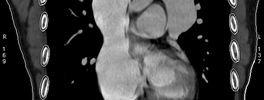

CT Heart

• Calcium scoring and coronary angiography